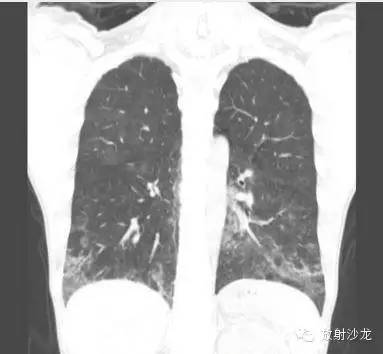

首次就诊胸片:

胸片示两肺中下野边界不清的磨玻璃样阴影(GGO)。CT示两肺地图样分布的GGO,主要位于两肺上叶、右肺中叶及两肺下叶,其中两肺下叶多发的GGO融合并伴有小叶间隔增厚。2周后随访胸片示双肺野弥漫分布的GGO增多。患者第一次就诊时未告知自己的性取向。只告知了曾接触过染发剂。患者按肺间质性疾病给予激素治疗。然而,治疗后患者的症状和影像学表现均加重。患者血液检测结果显示艾滋病病毒阳性。支气管肺泡灌洗液GMS染色示大量的卡氏肺孢子虫。